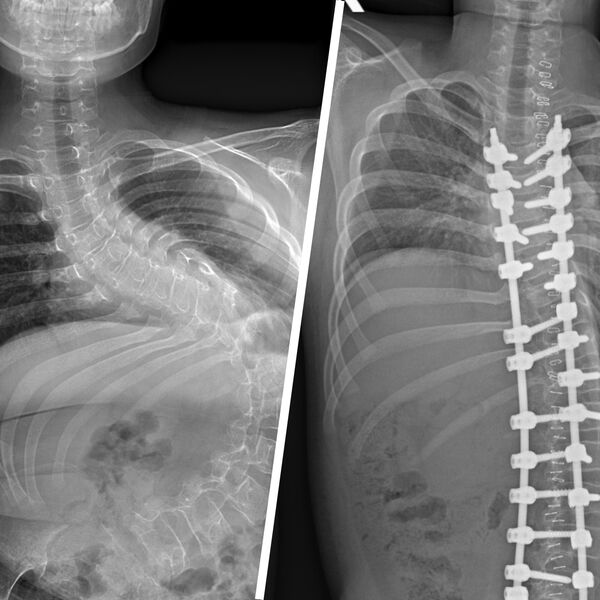

«Первым этапом хирургического лечения стала коррекция деформации позвоночника, поскольку она достигла уже критических значений — более 140 градусов искривления. Без своевременно выполненной операции сколиоз прогрессировал бы дальше, и мальчик не смог бы даже сидеть», — рассказал врач больницы Александр Васюра.

Вмешательство длилось четыре часа: за это время ребенку скрепили позвоночник металлической конструкцией, скорректировав деформацию до 32 градусов.